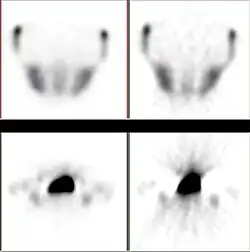

The advantages of the iterative approach include improved insensitivity to noise and capability of reconstructing an optimal image in the case of incomplete data. The method has been applied in emission tomography modalities like SPECT and PET, where there is significant attenuation along ray paths and noise statistics are relatively poor.

Statistical, likelihood-based approaches: Statistical, likelihood-based iterative expectation-maximization algorithms[7][8] are now the preferred method of reconstruction. Such algorithms compute estimates of the likely distribution of annihilation events that led to the measured data, based on statistical principle, often providing better noise profiles and resistance to the streak artifacts common with FBP. Since the density of radioactive tracer is a function in a function space, therefore of extremely high-dimensions, methods which regularize the maximum-likelihood solution turning it towards penalized or maximum a-posteriori methods can have significant advantages for low counts. Examples such as Ulf Grenander's Sieve estimator[9][10] or Bayes penalty methods,[11][12] or via I.J. Good's roughness method[13][14] may yield superior performance to expectation-maximization-based methods which involve a Poisson likelihood function only.